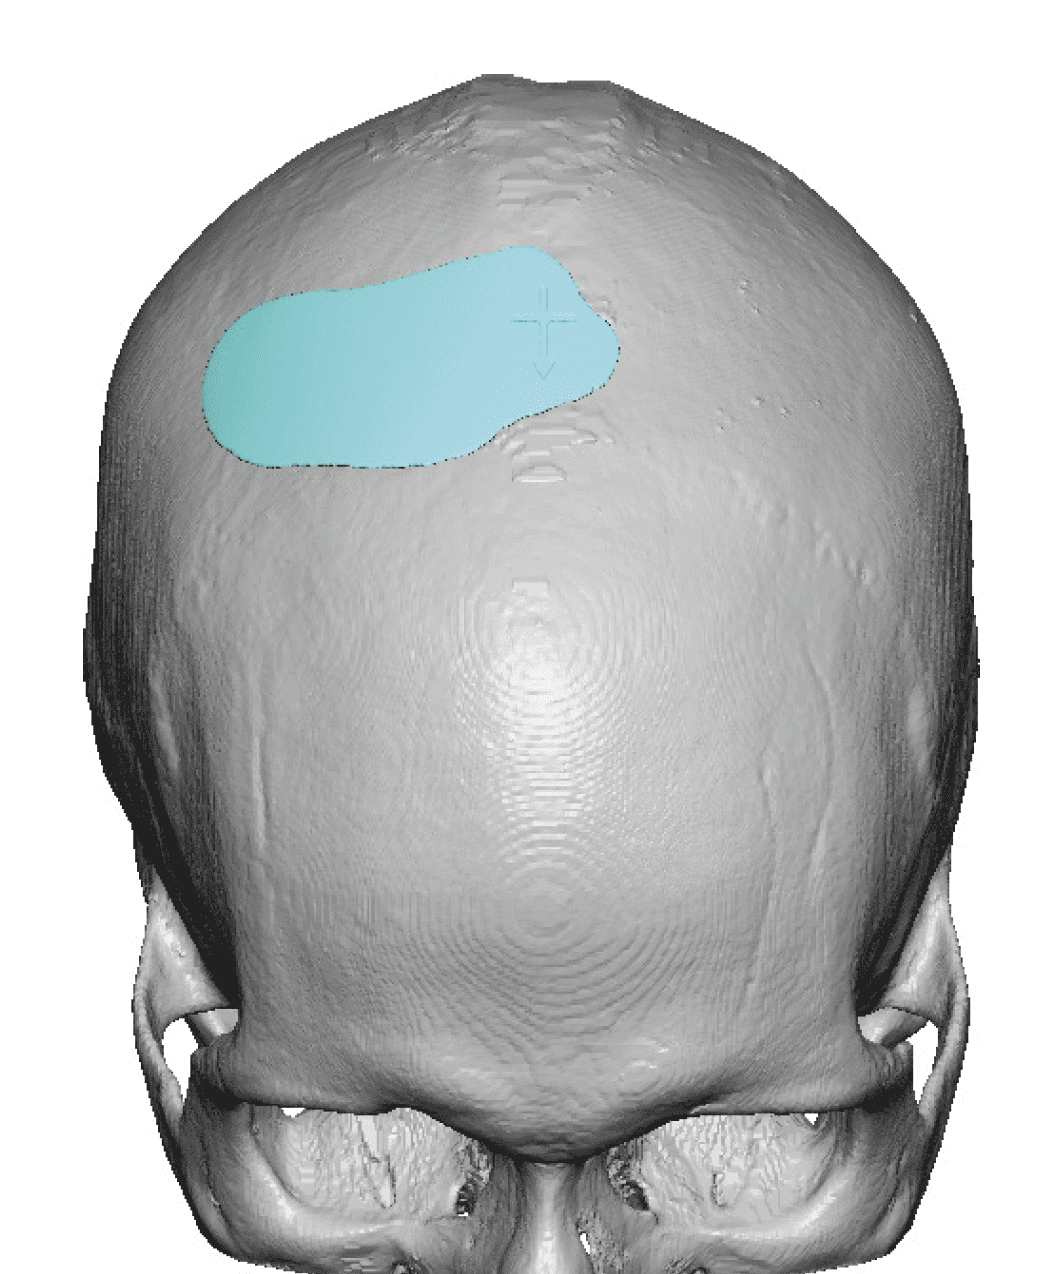

Patient 100

Desire for reshaping of an asymmetric flat back of the head in a shaved head male.

A combined back of the head reshaping procedure was done with a custom skull implant, sagittal ridge reduction and a right temporal muscle reduction.

Desire for reshaping of an asymmetric flat back of the head in a shaved head male.

A combined back of the head reshaping procedure was done with a custom skull implant, sagittal ridge reduction and a right temporal muscle reduction.